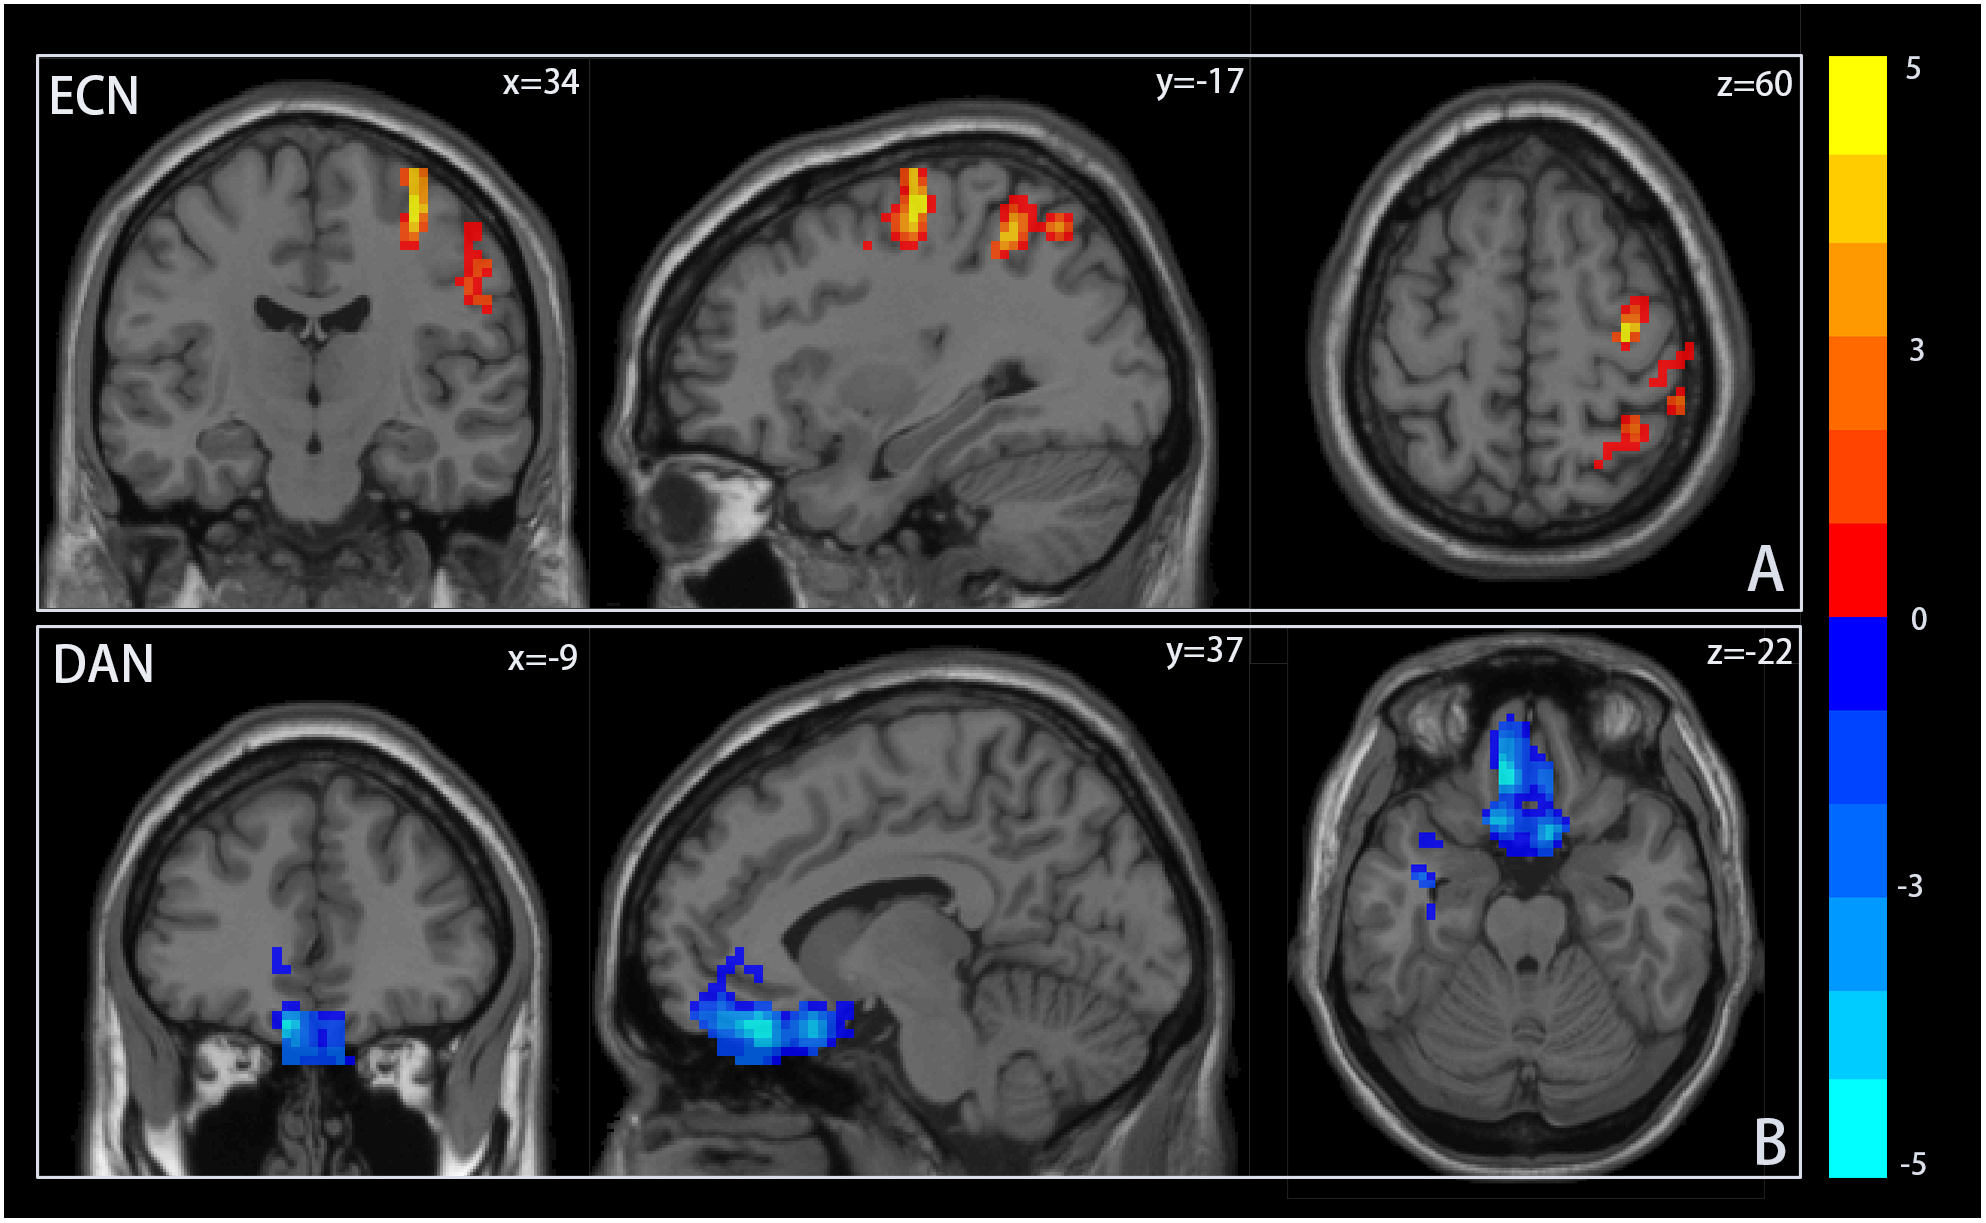

To assess differences in resting-state activity within ICNs associated with adolescent IGD, a two-sample t-test was utilized. Figure 2 displays brain regions with significant differences between groups. Adolescent IGD participants exhibited enhanced resting-state activity in the middle frontal gyrus (MFG) and precentral gyrus, part of the dLPFC, a key node of the ECN, compared to the HC group. In contrast, resting-state activity in the frontal eye field (FEF) of the DAN was diminished. Refer to Table 2. No differences in resting-state activity related to adolescent IGD were detected in other ICNs at the same significance threshold.

Figure 2. Resting-state activity differences within ICNs. Notes: (A) Resting state activity in the frontal gyrus and precentral gyrus within the executive control network(ECN) was significantly higher in the adolescent group with Internet Gaming Disorder (IGD) than in the healthy control group (HC). (B) In contrast, resting state activity in the frontal eye area within dorsal attention network(DAN) was significantly reduced compared to the HC group. Areas in red or blue indicate increased or decreased resting state activity, respectively.